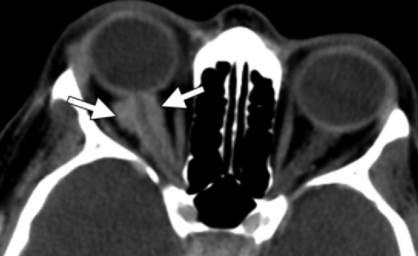

Méningiome de la gaine du nerf optique

- Intra-conale

- Prise de contraste

- Epargne du nerf optique

- Apparence de rails de tram